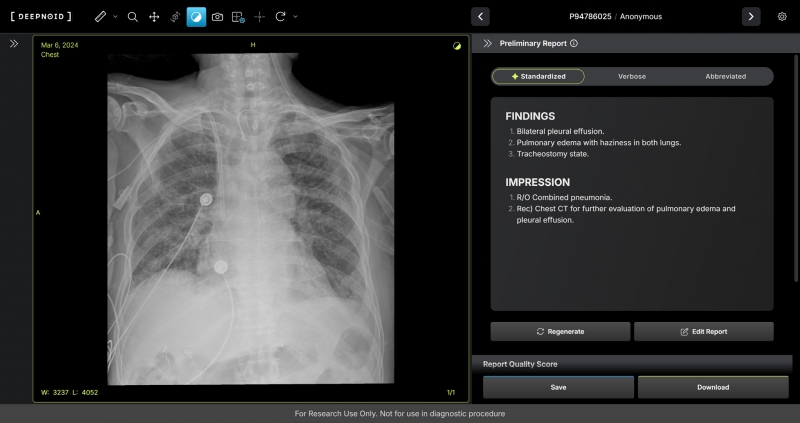

M4CXR은 흉부 X-ray 영상에서 41종의 병변을 판독해 수초 만에 일관성 있고 신뢰성 높은 판독소견서 초안을 작성한다.

이는 흉부 X-ray 영상과 대응되는 1000만건 이상의 판독소견서 데이터를 학습해 구현된 기술로, 특히 응급상황에서 의료진이 즉시 예비 판독 결과를 받을 수 있어 중요한 임상 결정과 환자 진료에 더욱 집중할 수 있도록 지원하며 영상의학과 전문의 판독을 보조한다.